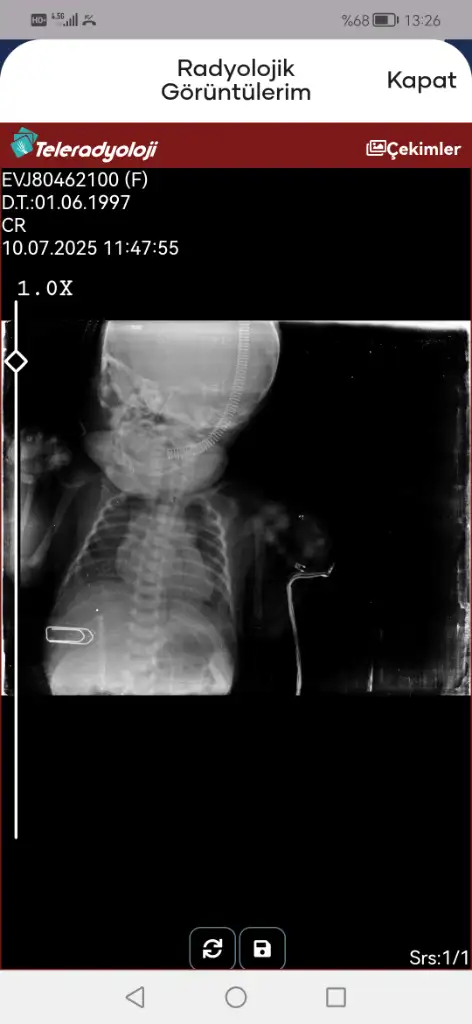

Evet entübasyon hortumu görünmüyor iki hortum olmalıydı ağzında. Entübeden ayrılması da iyi bir şey süt de azıcık gaz yapmış hatta bebişe. Süt aldıkça bu değerler toparlanır. Kan gazına göre bebeğiniz solunumu tölere edebiliyor diyebiliriz bunlar güzel haberler

Eklentiler

• Screenshot_20250709_142908_tr.gov.saglik.enabiz.webp

Screenshot_20250709_142908_tr.gov.saglik.enabiz.webp